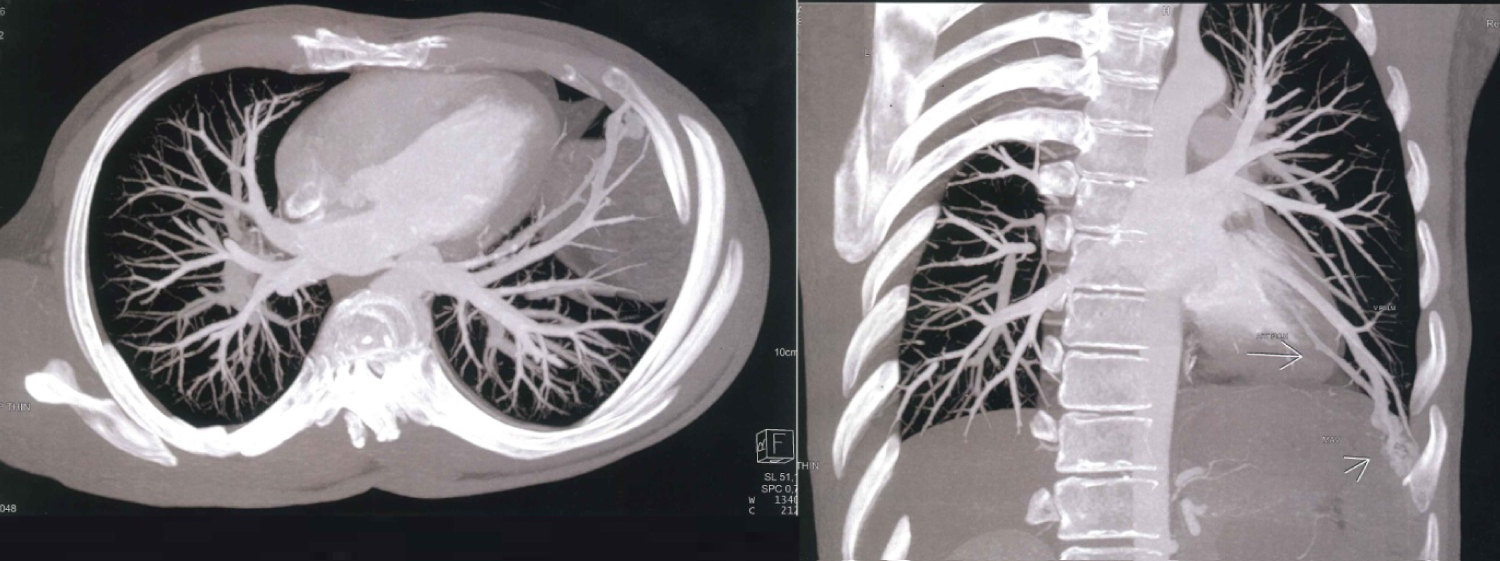

The chest CT scan did not reveal any lesional process, but did show a varicose appearance involving the antero-basal segment of the left lower lobe of vascular type, causing the pulmonary vein to communicate distally with the pulmonary artery (Figure 1). A thoracic angioscan with arterial and venous time, and a three-dimensional reconstruction was performed, confirmed the diagnosis of MAVP, showing an abnormally dilated aspect of the left lower lobe pulmonary vein, measured at 5 mm, who's followed to its distality leads to a sacciform formation, extended over 17 mm, with venous return, measured at 2.5 mm and communicating with the lower lobar of the left pulmonary artery (Figure 2).

Figure 1: CT scan showing the unusual arteriovenous communication in the left lower lobe (arrow) between the antero-basal pulmonary artery trunk and the lower pulmonary vein. View Figure 1